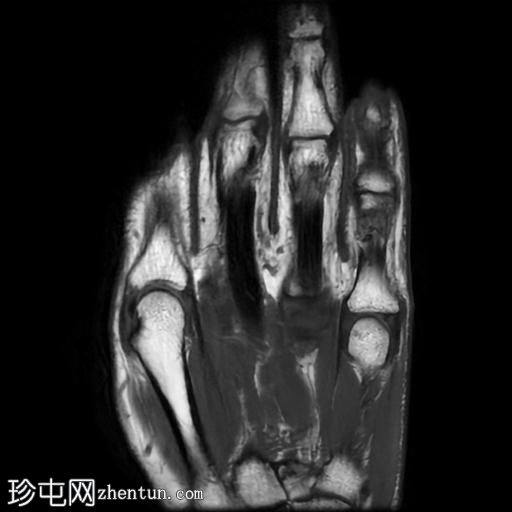

MRI

矢状位

T1加权像

PD脂肪抑制像

冠状位PD脂肪抑制像

轴位

轴位PD脂肪抑制像

冠状位

T2加权像

第五指小指伸肌腱远端纤维完全撕裂,伴远端指间关节屈曲畸形。

撕裂肌腱近端位于第五指中节指骨头附近,止点与近端撕裂处之间约有4毫米的间隙。

患者左手受伤,导致第五指小指伸肌腱远端止点纤维完全撕裂,并伴有槌状指畸形。